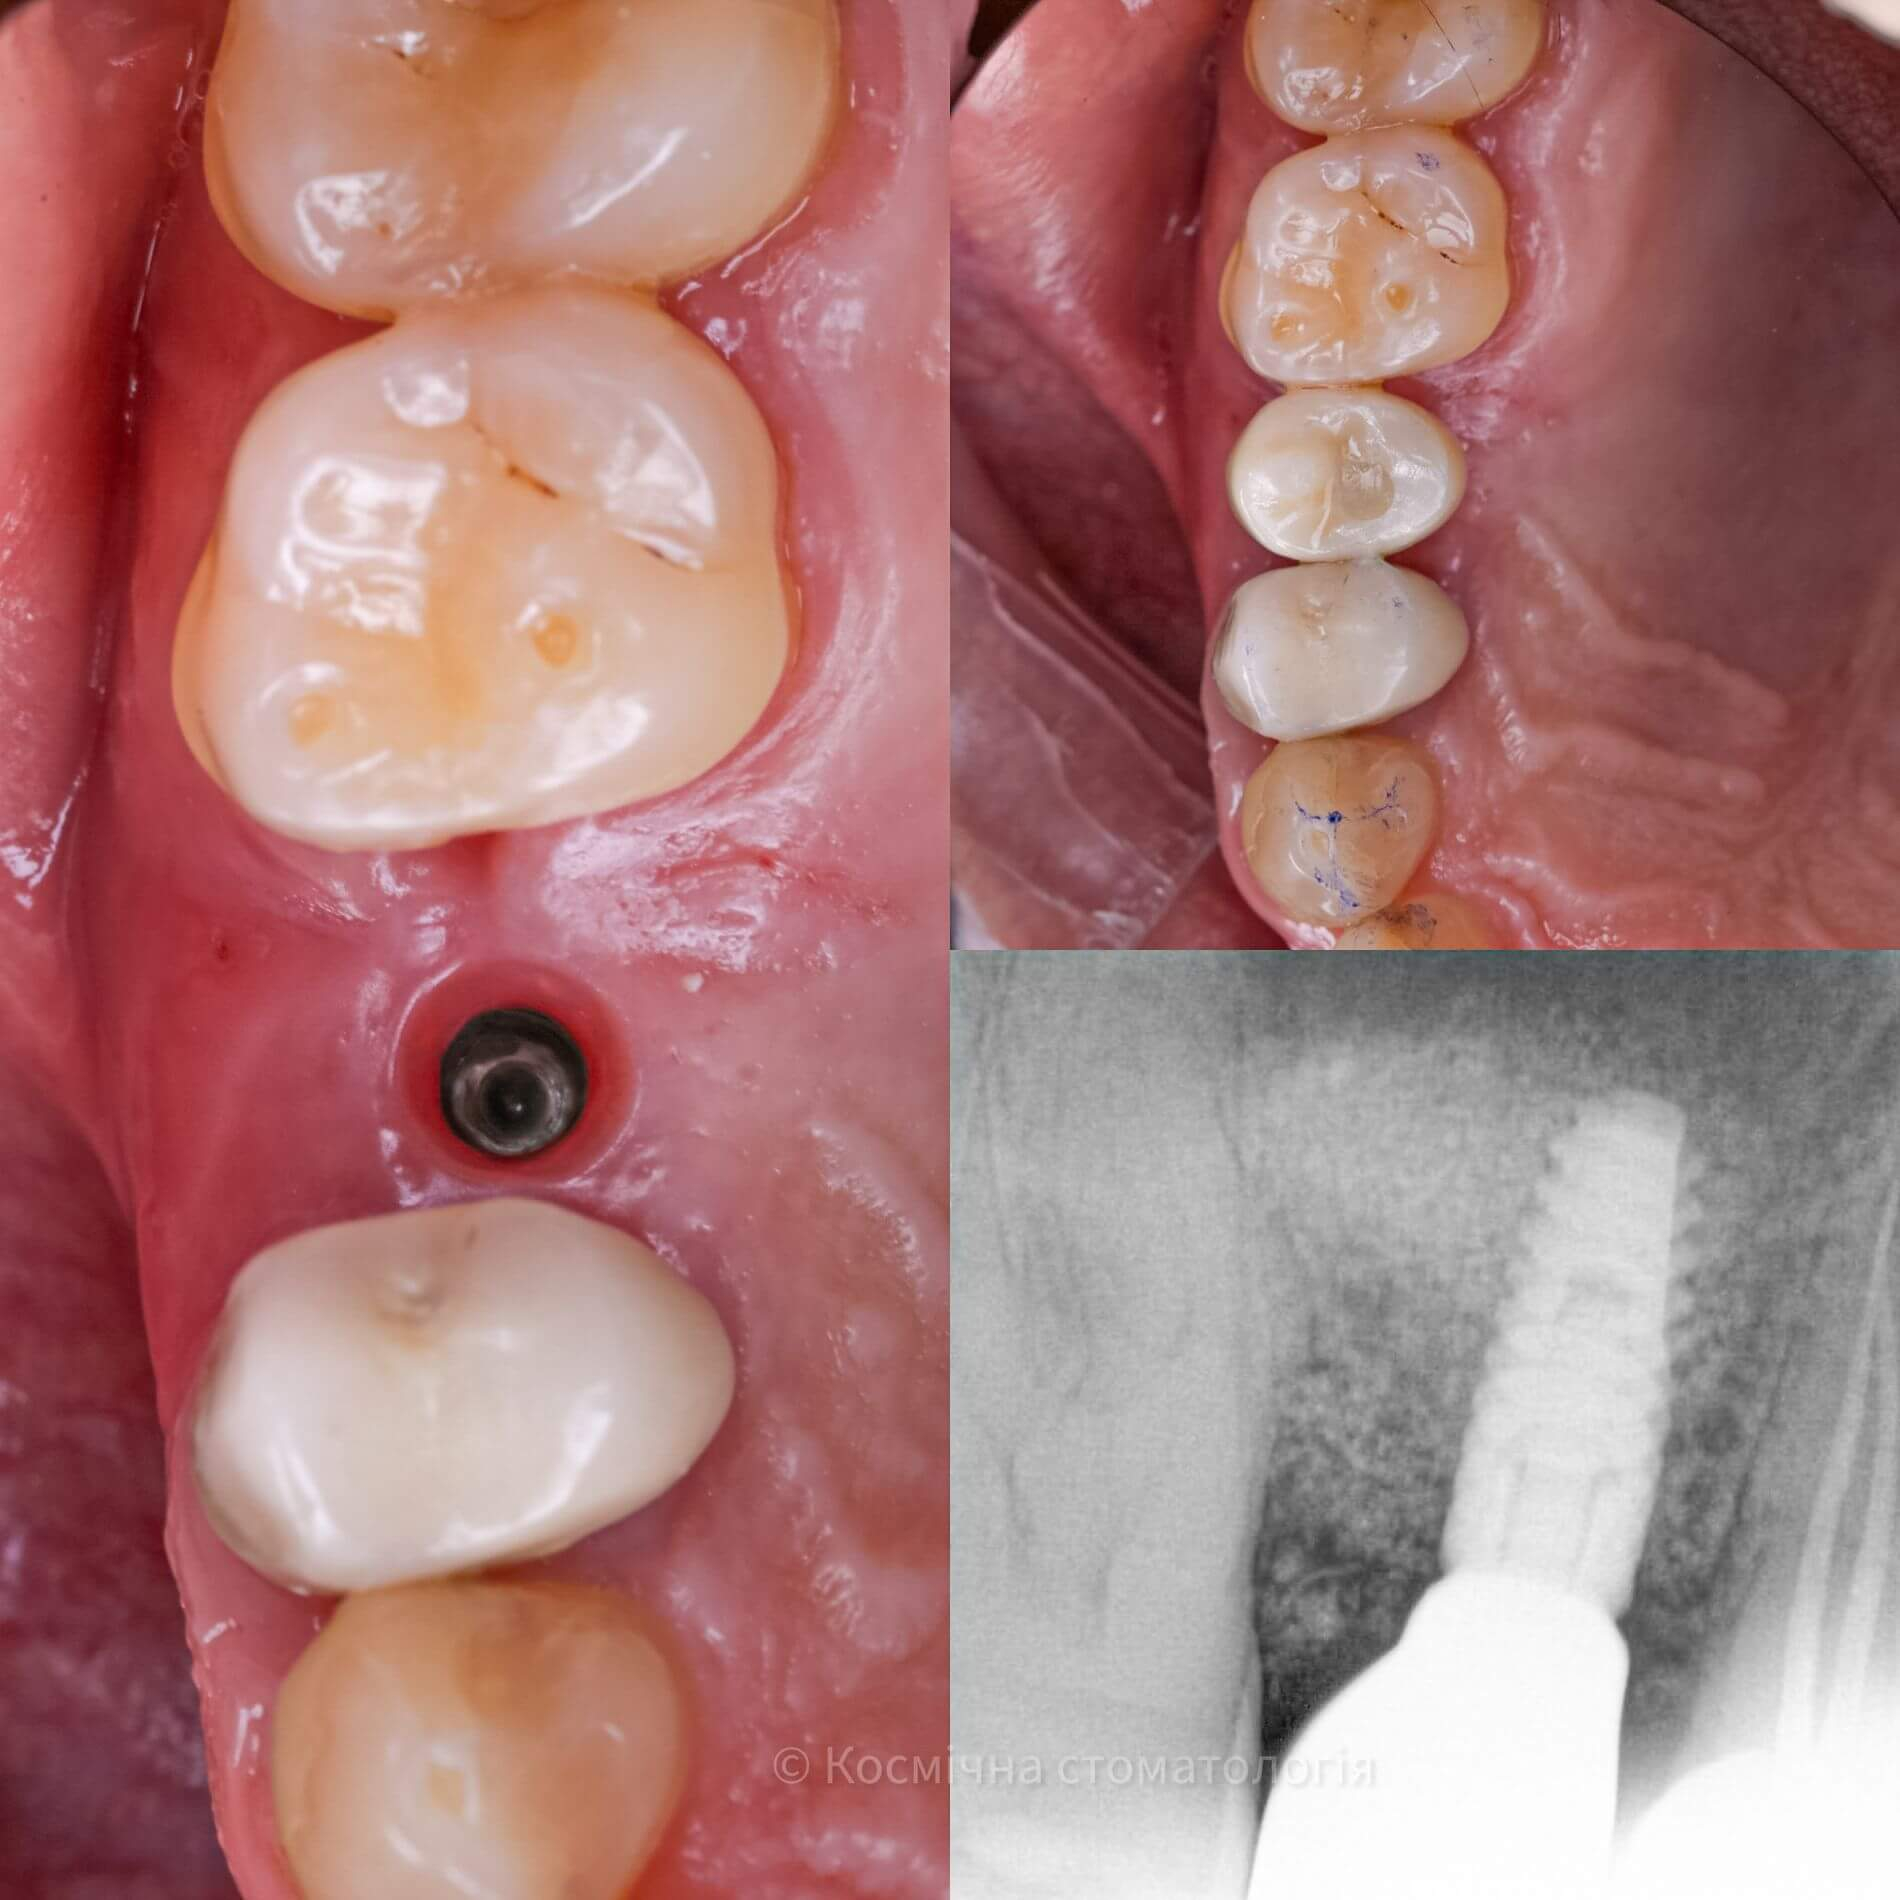

Галерея